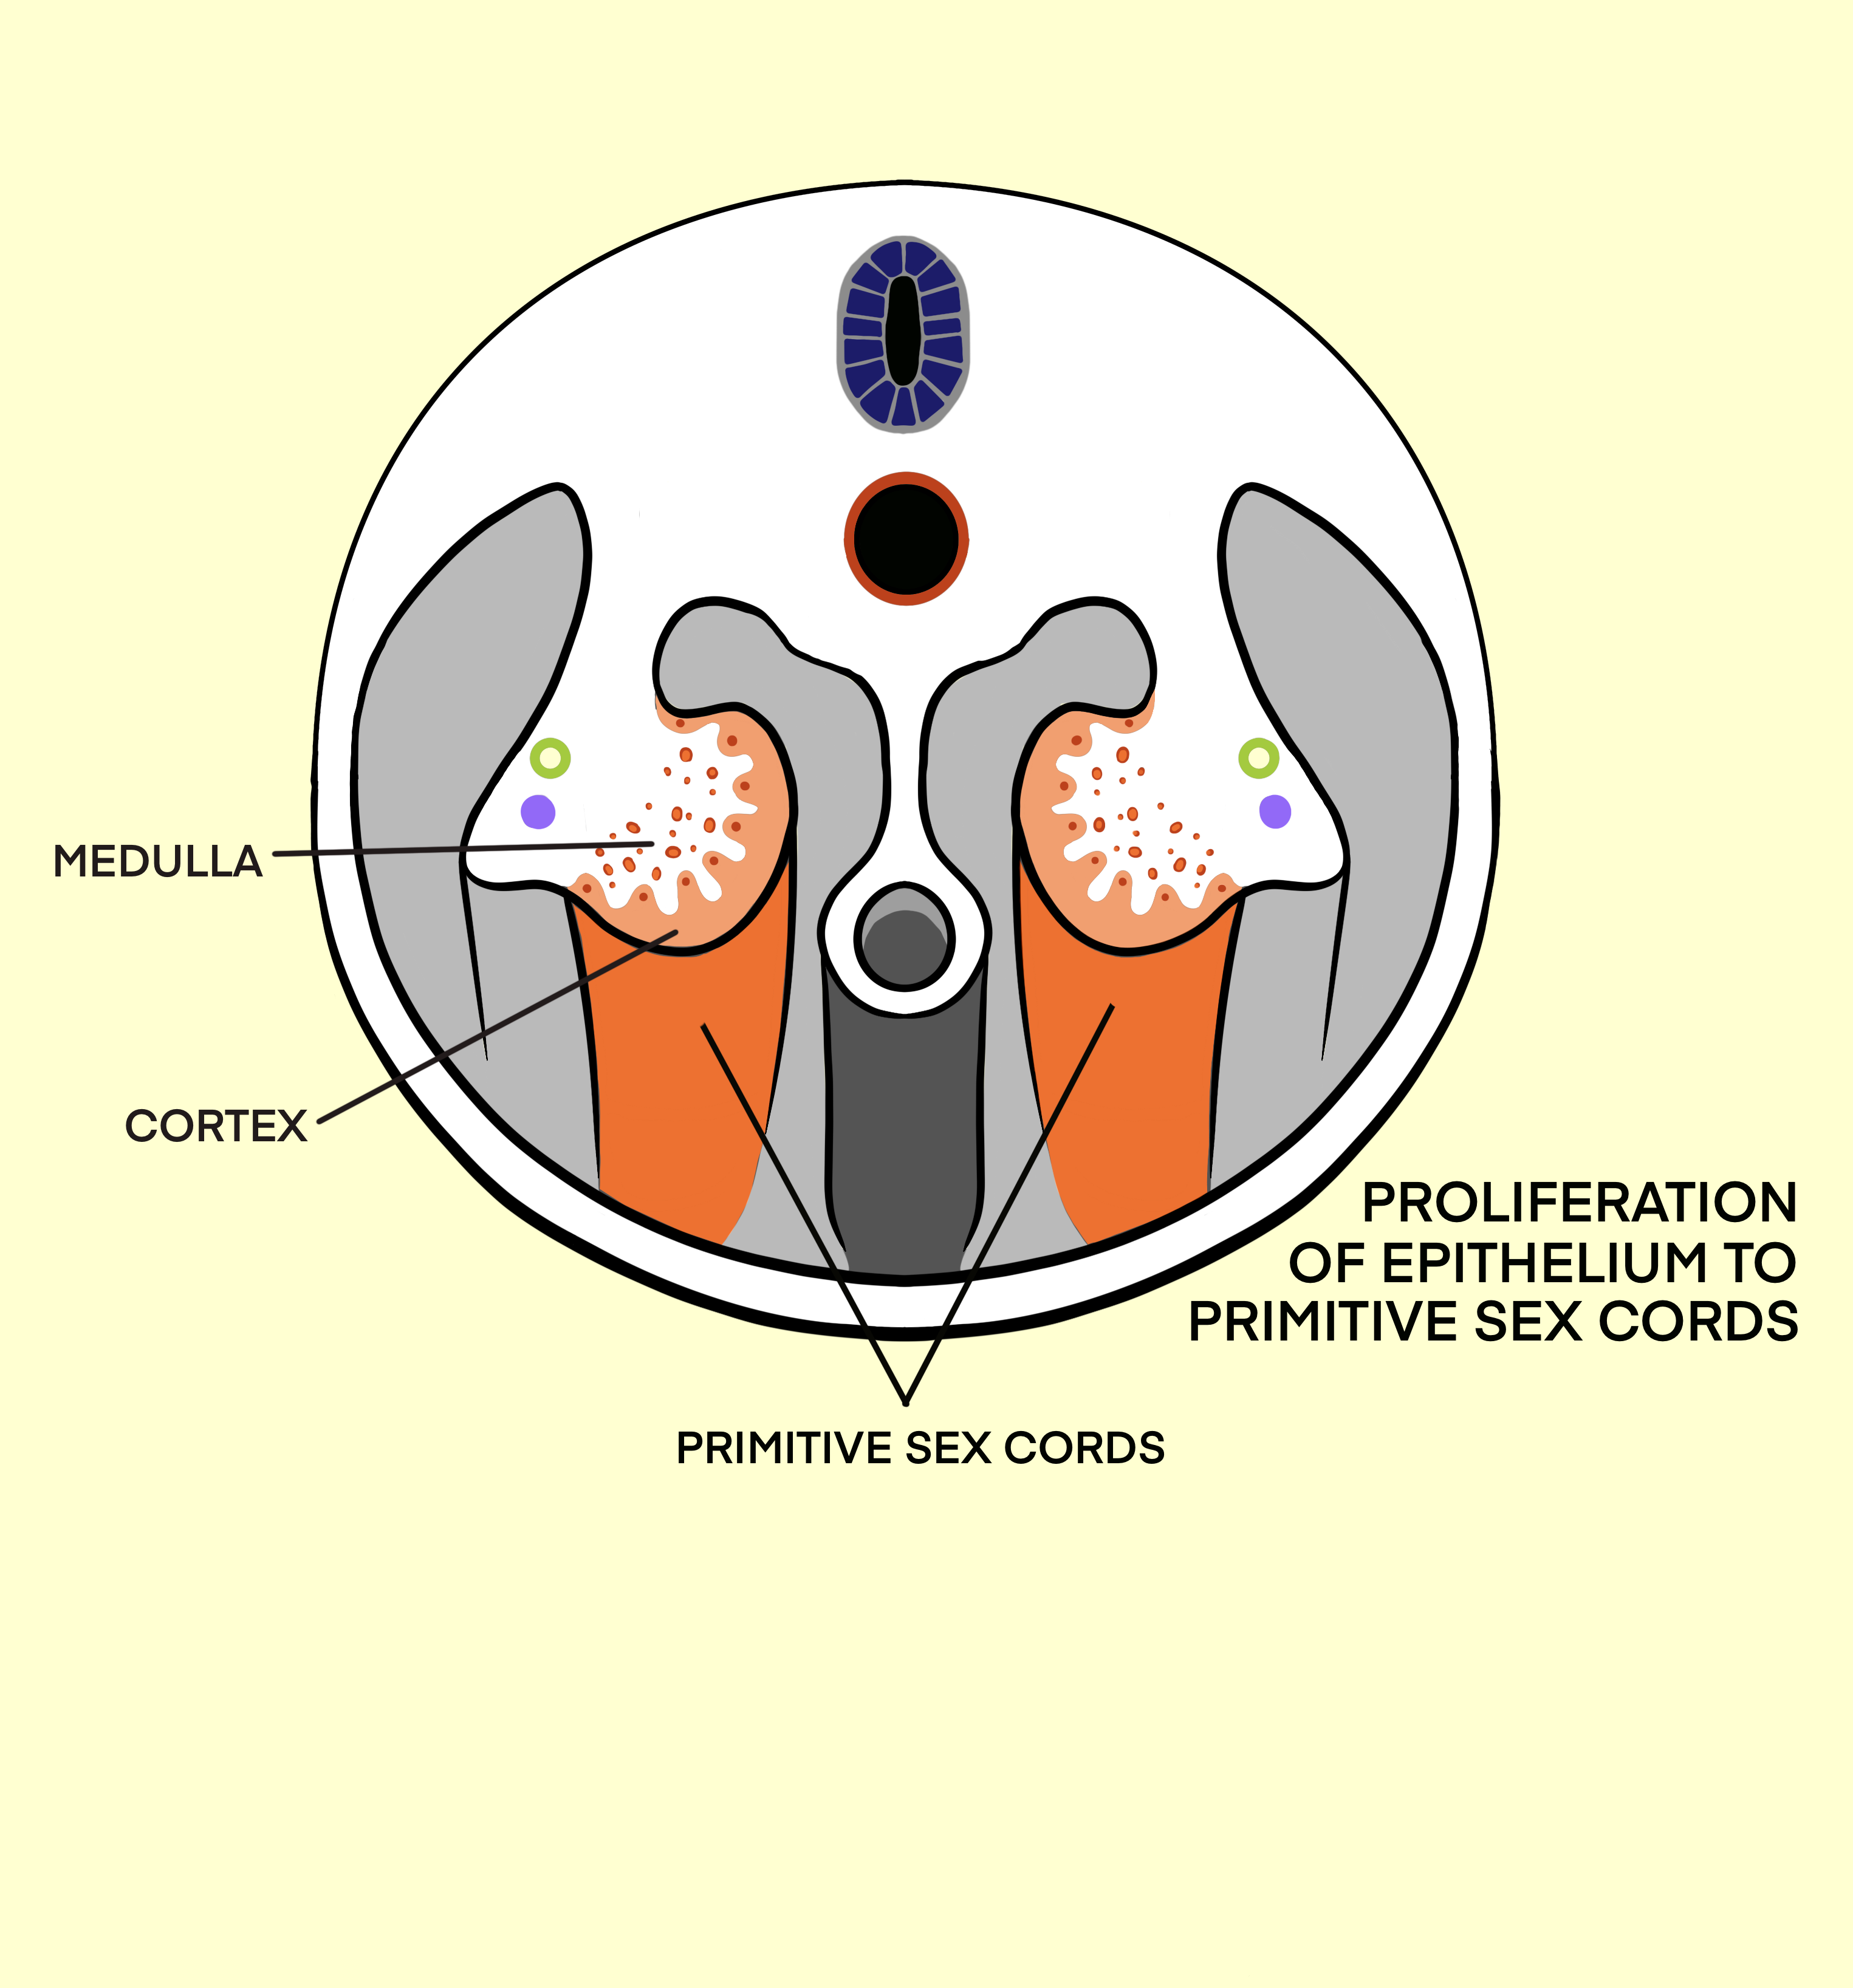

Development of the Genital System